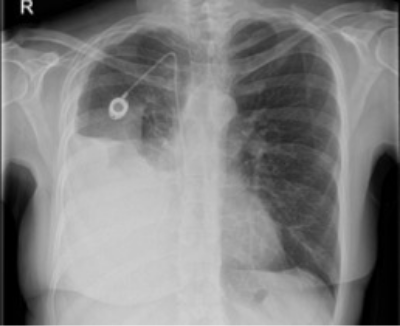

Chest X-ray depicting right pleural effusion6

Image provided by Prof Mohammed Munavvar

Clinical image taken with patient's permission